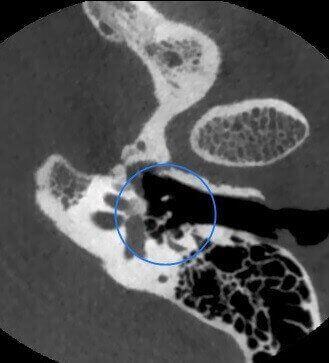

Catena Ossiculare e Nervo Facciale